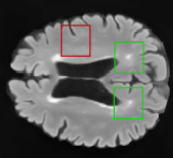

In order to analyze qualitatively the results of our generator, we extract slices with different WMHs loads, Table 4 shows the reconstruction results for three different levels of loads. As we can see in the first row, both methods produce a similar response in regions with a low load of lesions, it can be observed that generated images are similar to the real FLAIR images in the left, and these not present evident structural distortions. However, it can be noted images exhibit blurred effects, which can be due to L2 based optimization, more complex generative networks with adversarial loss optimization as GANs tend to eliminate blurred effect but at the expense to produce structural distortions. In the application presented in this work it is important to preserve the structural information, thus, our L2 based optimization present a good balance between preserve structural information and blurred effects. In the second and third column, it can be observed the performance of both methods when facing the presence of lesions, as can be seen, both methods have a good response to large and contiguous lesions. It also can be noted both methods tend to produce poor performance in small and diffuse WMHs marked in red, note, these lesion do not exhibit identifiable patterns in T1 images, however it can be seen that our proposed method is more sensitive to these patterns which enable to highlight some small regions as those marked in green.

FLAIR T1 Offline synthesis Proposal

[Uncaptioned image] [Uncaptioned image] [Uncaptioned image] [Uncaptioned image]

Table 4: Results of Generation for all the proposed methods,